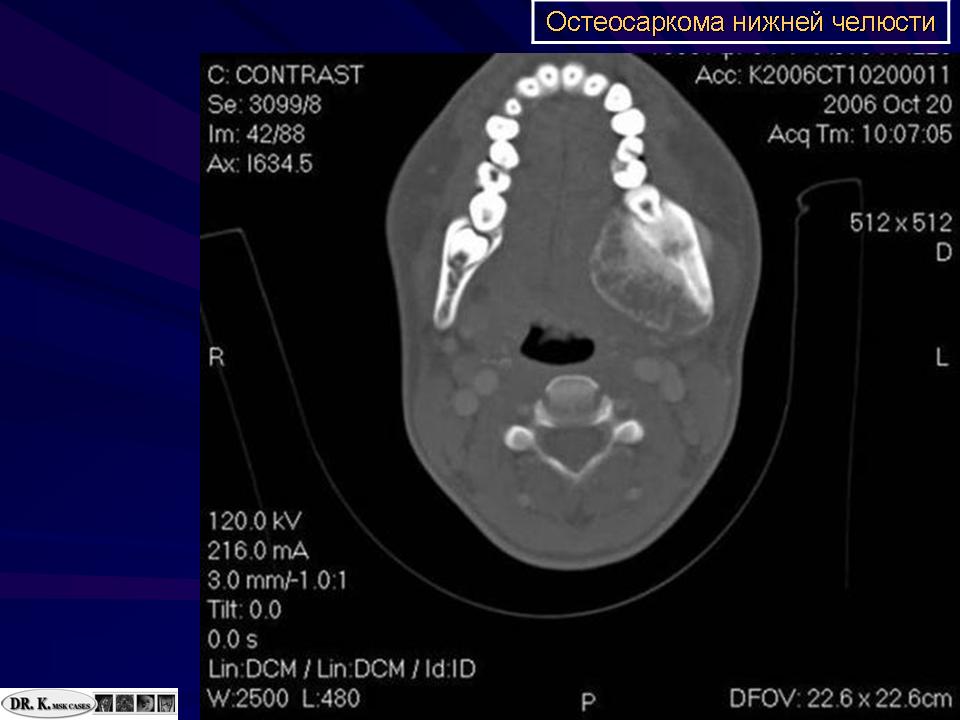

Кисты и костоподобные образования нижней челюсти

http://radiographics.rsna.org/content/19/5/1107.full